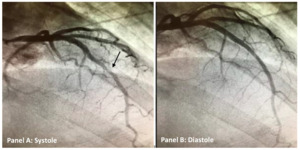

The patient was admitted to the hospital for non-ST elevation myocardial infarction and guideline directed medical therapy with anti-coagulation using intravenous heparin and anti-platelet therapy using aspirin was instituted. Anti-coagulants are a class of medications commonly referred to as blood thinners. They are used to prevent coagulation of blood and to prolong the clotting time.5 Coronary angiography was performed as the patient was having persistent chest pain despite optimal medical therapy and supportive care including nitrates and anti-anginal agents. Nitrates are a class of medication commonly used during acute coronary syndromes for symptomatic relief. Coronary angiography revealed normal coronary arteries with myocardial bridging of the mid-left anterior descending artery (Figure 2A-B). Since patient coronary arteries were unremarkable for any stenosis per angiography, intravascular ultrasound technique was not utilized. Intravascular ultrasound is a type of imaging used frequently to assess for atheromatous plaque burden in coronary arteries.6